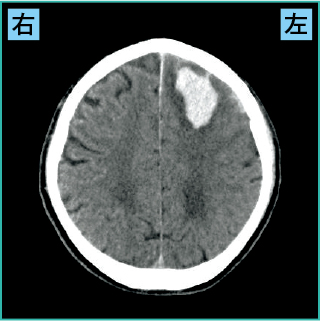

3)皮質下出血の画像の見方

図4は皮質下出血の画像です。

図4 皮質下出血(CT)

責任血管は前・中・後大脳動脈から分岐した血管です。皮質とは大脳皮質のことで、大脳の表面の部分をいいます。

皮質下出血は、部位によって症状が異なります。

図4の症例では左の前頭葉の障害により、右上下肢の運動麻痺が出現していました。

なお皮質下出血は、“高血圧性脳出血以外”の脳出血のアミロイドアンギオパチー*1や脳動静脈奇形*2が原因の脳出血が多く見られます。

また皮質下出血では、けいれんの可能性を念頭に置く必要があります(詳細は後述)。